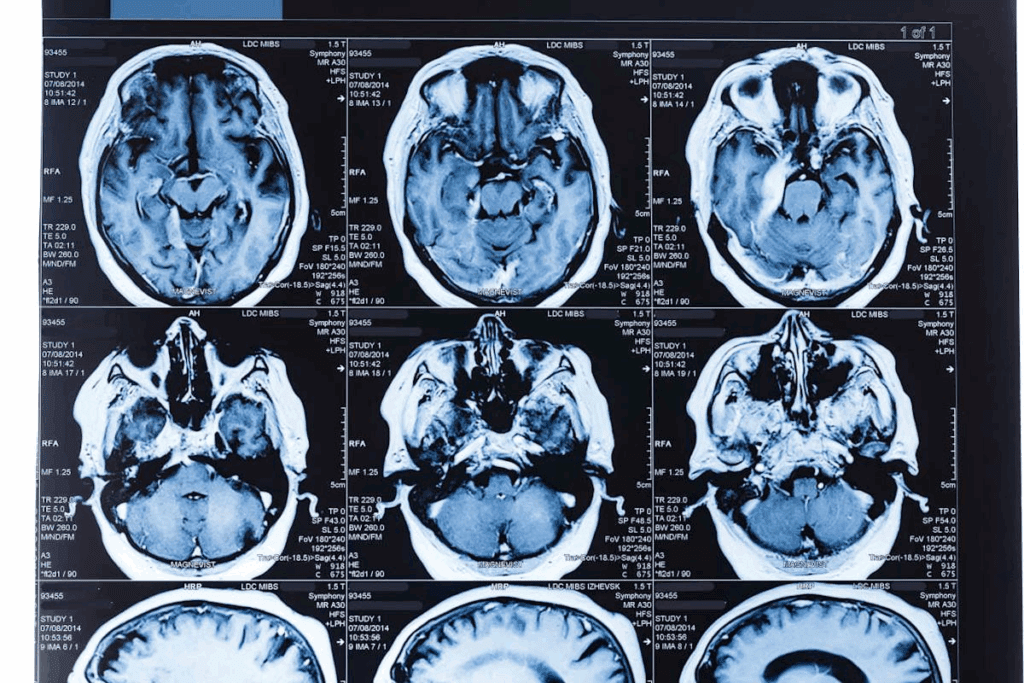

Neuroimaging and Brain Scans

Neuroimaging is vital for diagnosing brain tumors and ruling out other causes of symptoms. MRI and CT scans give us detailed brain images.

| Imaging Technique | Primary Use | Benefits |

| MRI | Detailed soft tissue imaging | High sensitivity for detecting tumors and structural abnormalities |

| CT Scan | Quick assessment of brain structures | Useful in emergency settings and for patients with certain metal implants |